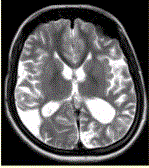

问题 女性,22岁。癫痫发作及智力异常。MRI显示见下图。 有关该病的描述,正确的是

选项 A.多种原因引起颅底大动脉严重狭窄或闭锁,并可见脑底部代偿性异常血管网 B.MRT2WI显示基底节区多发点状血管流空信号 C.DSA显示willis环闭塞,颅底区烟雾状侧支循环 D.CT显示低密度病灶,为缺血、梗死所致,特征是双侧性和多发性 E.影像学首选MRA及MRI F.主要发生在老年人 G.多见于颈内动脉床突上段和大脑前、中动脉近段和基底动脉远端

答案 ABCDEG